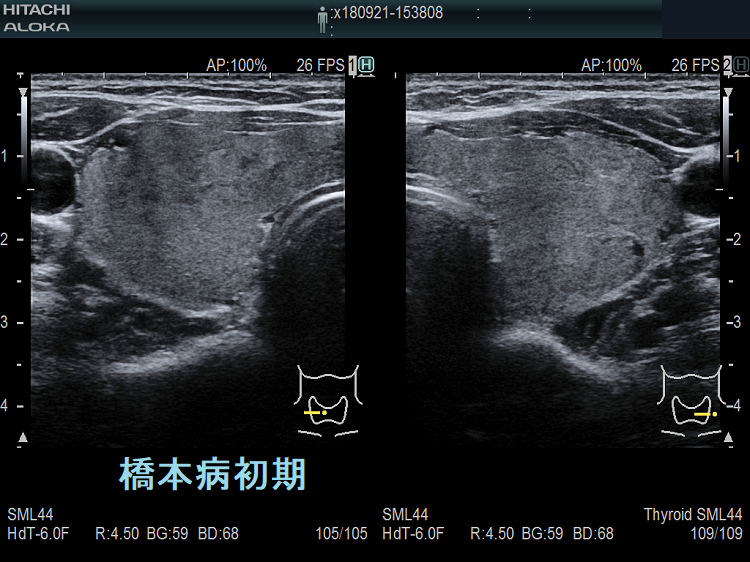

橋本病初期エラストグラフィー

橋本病(慢性甲状腺炎);中等度の破壊性変化

橋本病(慢性甲状腺炎);中等度の破壊性変化。線維化が進んでいないのでが主体になります。